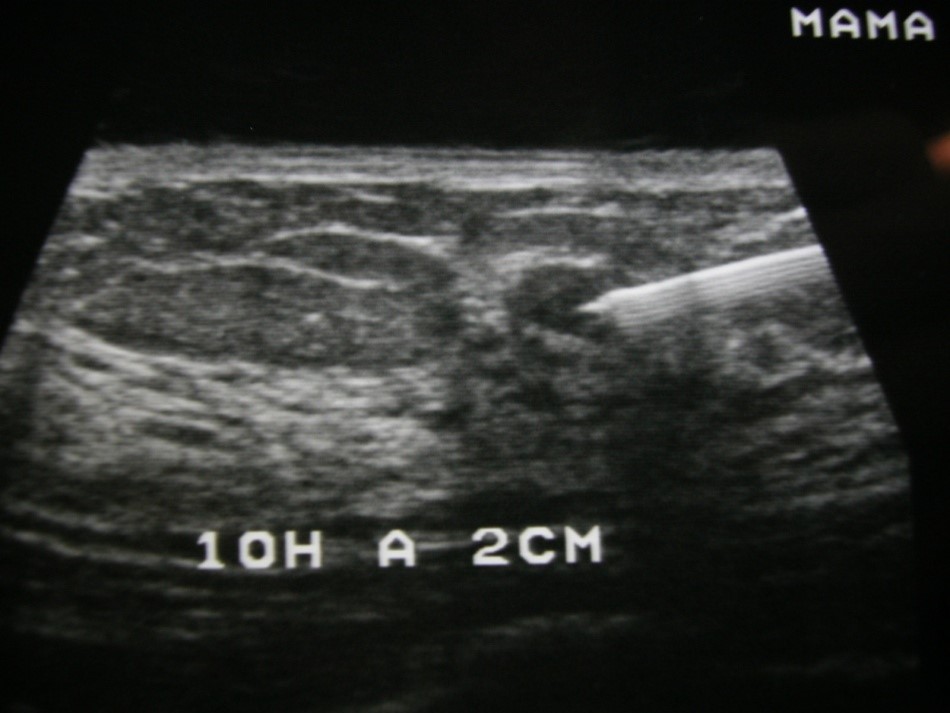

Ecografia/Ultrassonografia

É um método de diagnóstico por imagem não invasivo, sem uso de radiação ionizante, que permite estudo de estruturas anatômicas do corpo.

Procedimentos minimamente invasivos

Biópsia de Mama, de Tireóide e de Estruturas Superficiais; Demarcação Pré-cirúrgica de Mama; Demarcação Pré-quimioterápica de Mama com clipe Metálico